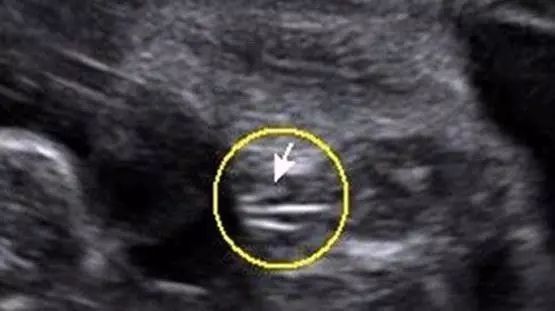

女宝宝的b超图

三条白线是明显的女宝特征,如果没有看到明显的三条白线,就看两腿之间有没有突出的东东,且中间有小凹槽的,就是女宝。